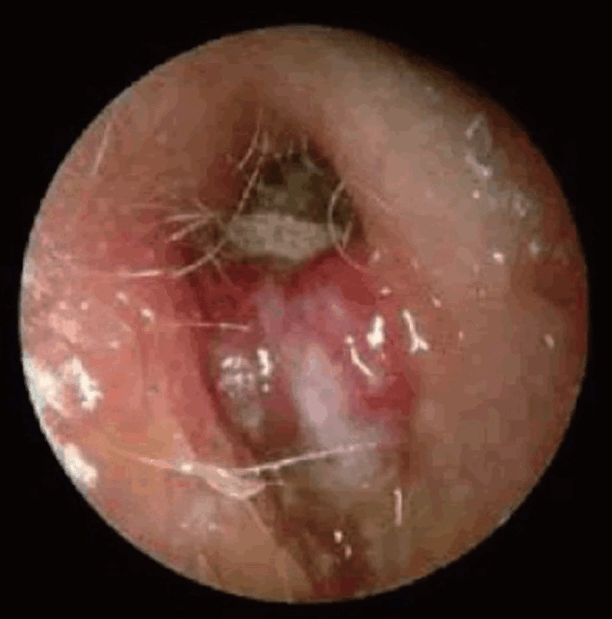

67세 남환이 2달 전부터 지속된 우측 이루를 주소로 내원하였다. 환자는 이전에는 이루를 경험한 적이 없으며, 2달간 인근 병원에서 항생제 치료를 받았으나 큰 호전이 없었다고 한다. 환자는 심한 통증으로 밤에는 잠들기 어렵다고 호소하였으며, 현재 고혈압과 당뇨로 약물 복용 중이나 혈당이 잘 조절되지 않는다고 한다. 다음은 환자의 고막 소견이다. 해당 질환에 대해 옳지 않은 것은?

본 질환은 급성 외이도염이 진행되어 발생한 괴사성 외이도염이다. 대부분의 환자가 고령, 당뇨병을 가지고 있으며 중등도 이상의 이통 및 외이도 뼈-연골 접합부에서 육아종이 관찰되는 것이 특징적이다. 이에 동반되는 뇌신경마비는 신경부종에 의한 압박에 의해 생기는 것이 아니라 신경 자체의 염증으로 생기는 것으로 신경 감압술(nerve decompression)은 도움이 되지 않을 수 있다.